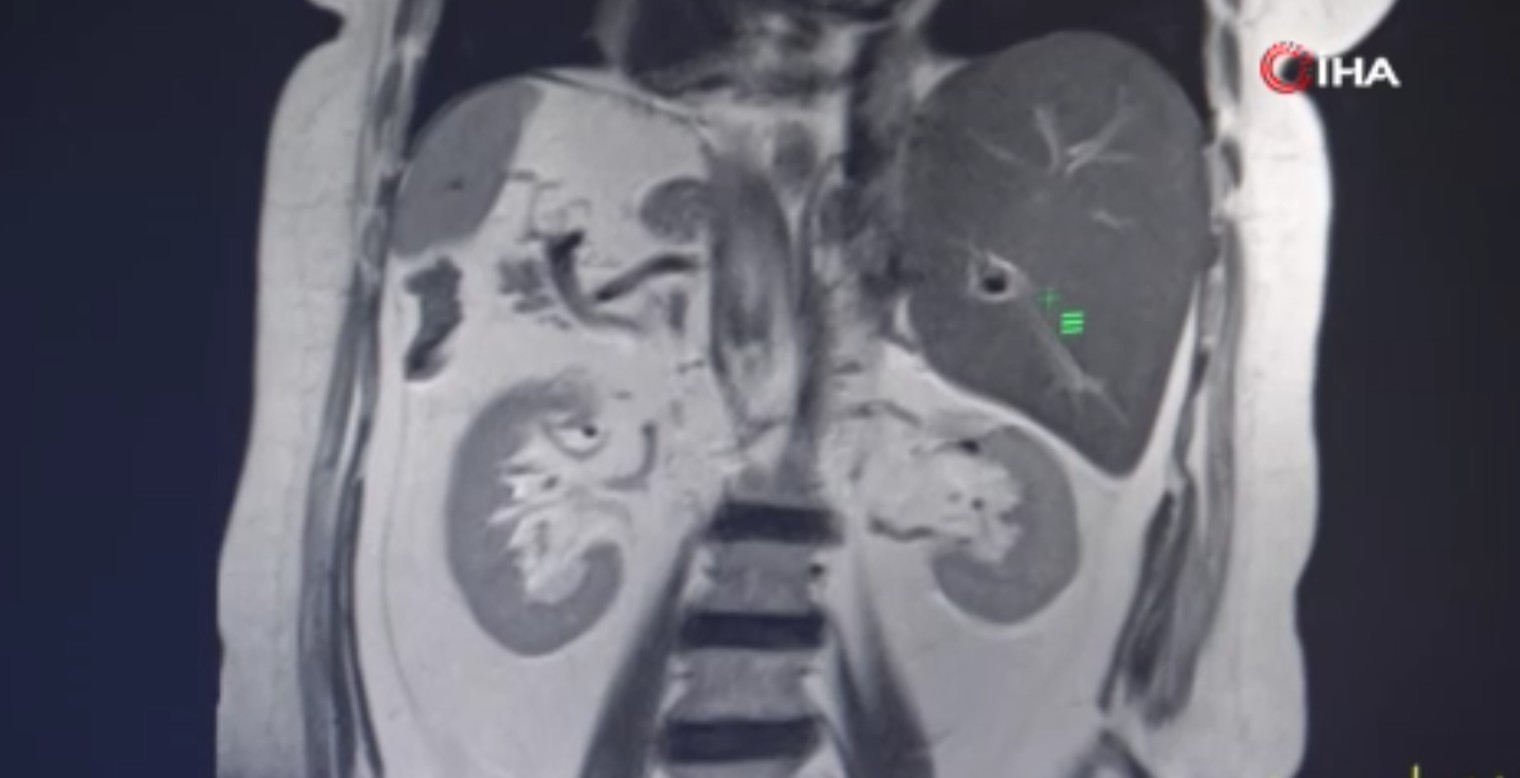

Son olarak Gaziantep Şehir Hastanesi'ne başvuran Evin Aslan'ın hastanede yapılan tetkikler sonucunda iç organlarının tamamının ters tarafta olduğu anlaşıldı. Kalp, mide, dalağı, göğüs ve karın bölgesinin sağında, karaciğer ve safra kesesinin ise solda olduğunu öğrenen Aslan, hayatının şokunu yaşadı.